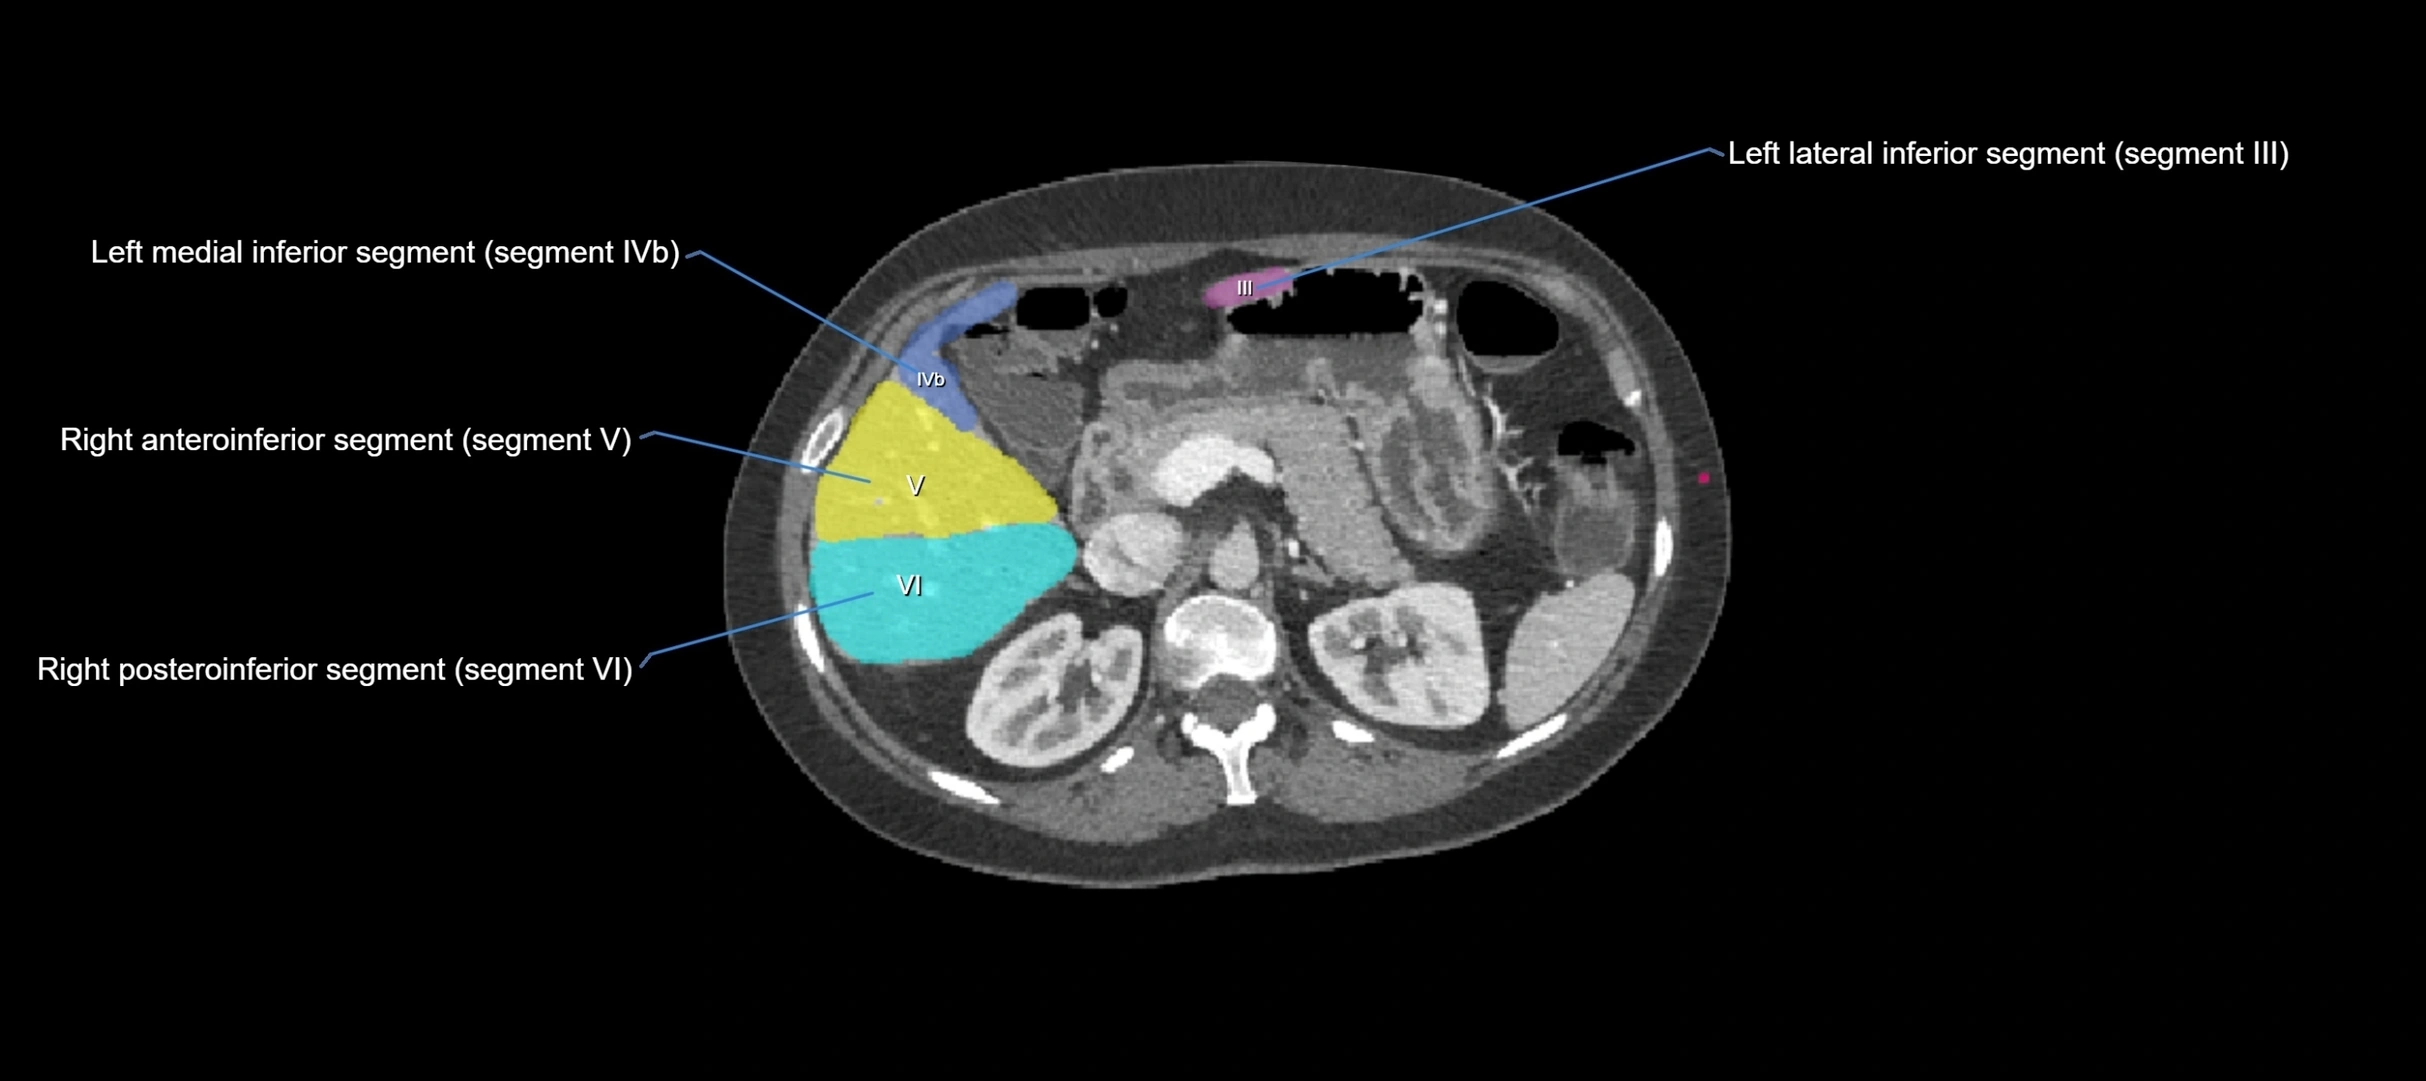

CT Image

image